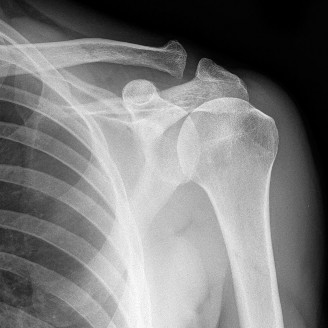

The correct answer is (B). An MRI showing a rotator cuff tear is considered diagnostic of a rotator cuff tear because of its high sensitivity, specificity, and accuracy. It has superb soft tissue imaging abilities (see Fig. 2–5). However, it should be noted that while MRI usually can differentiate between partial- and full-thickness rotator cuff tears, this varies with the power and accuracy of the MRI facility. This is also true with the ability of MRI to differentiate between partial-thickness rotator cuff tears and subacromial bursitis. An arthroscopy is needed for definitive differentiation of these pathologies.

Figure 2–5_Coronal oblique view MRI slice of a left shoulder. (Reproduced with permission from Smithius R and van de Woude HJ. Shoulder MR Anatomy: Normal Anatomy, Variants, and Checklist. _Radiology Assistant. April 2, 2012.)

Shoulder CT scans (Answer A) are not typically used to diagnose rotator cuff tears. X-rays, aka roentgenograms (Answer C), can show signs of rotator cuff pathology but are not diagnostic. Some signs of chronic rotator cuff tears that are sometimes seen on AP view x-rays include calcific tendonitis, calcification of the coracohumeral ligament, proximal migration of the humerus, and cystic changes of the greater tuberosity. An outlet view x-ray can show a type III (hooked) acromion, which is correlated with a higher rate of rotator cuff tears, or an OS acromiale, which would require special consideration for surgical treatment. Shoulder arthrograms (Answer D) are used primarily only when MRI is contraindicated and are considered positive for a rotator cuff tear if dye leaks from the glenohumeral joint into the subacromial space. MR arthrogram (Answer E) has been shown to have equivalent diagnostic ability compared with standard MRI and can be used to diagnose rotator cuff tears. However, it adds an additional step and cost to a standard MRI, and it does not offer any additional diagnostic benefit for rotator cuff pathology. Therefore, standard MRI is preferred to MR arthrogram.

Shoulder ultrasound is another modality that can be used to diagnose rotator cuff tears. It is generally less expensive than MRI but the sensitivity and specificity are more operator-dependent. Objectives: Did you learn...? Clinically diagnose a rotator cuff tear?